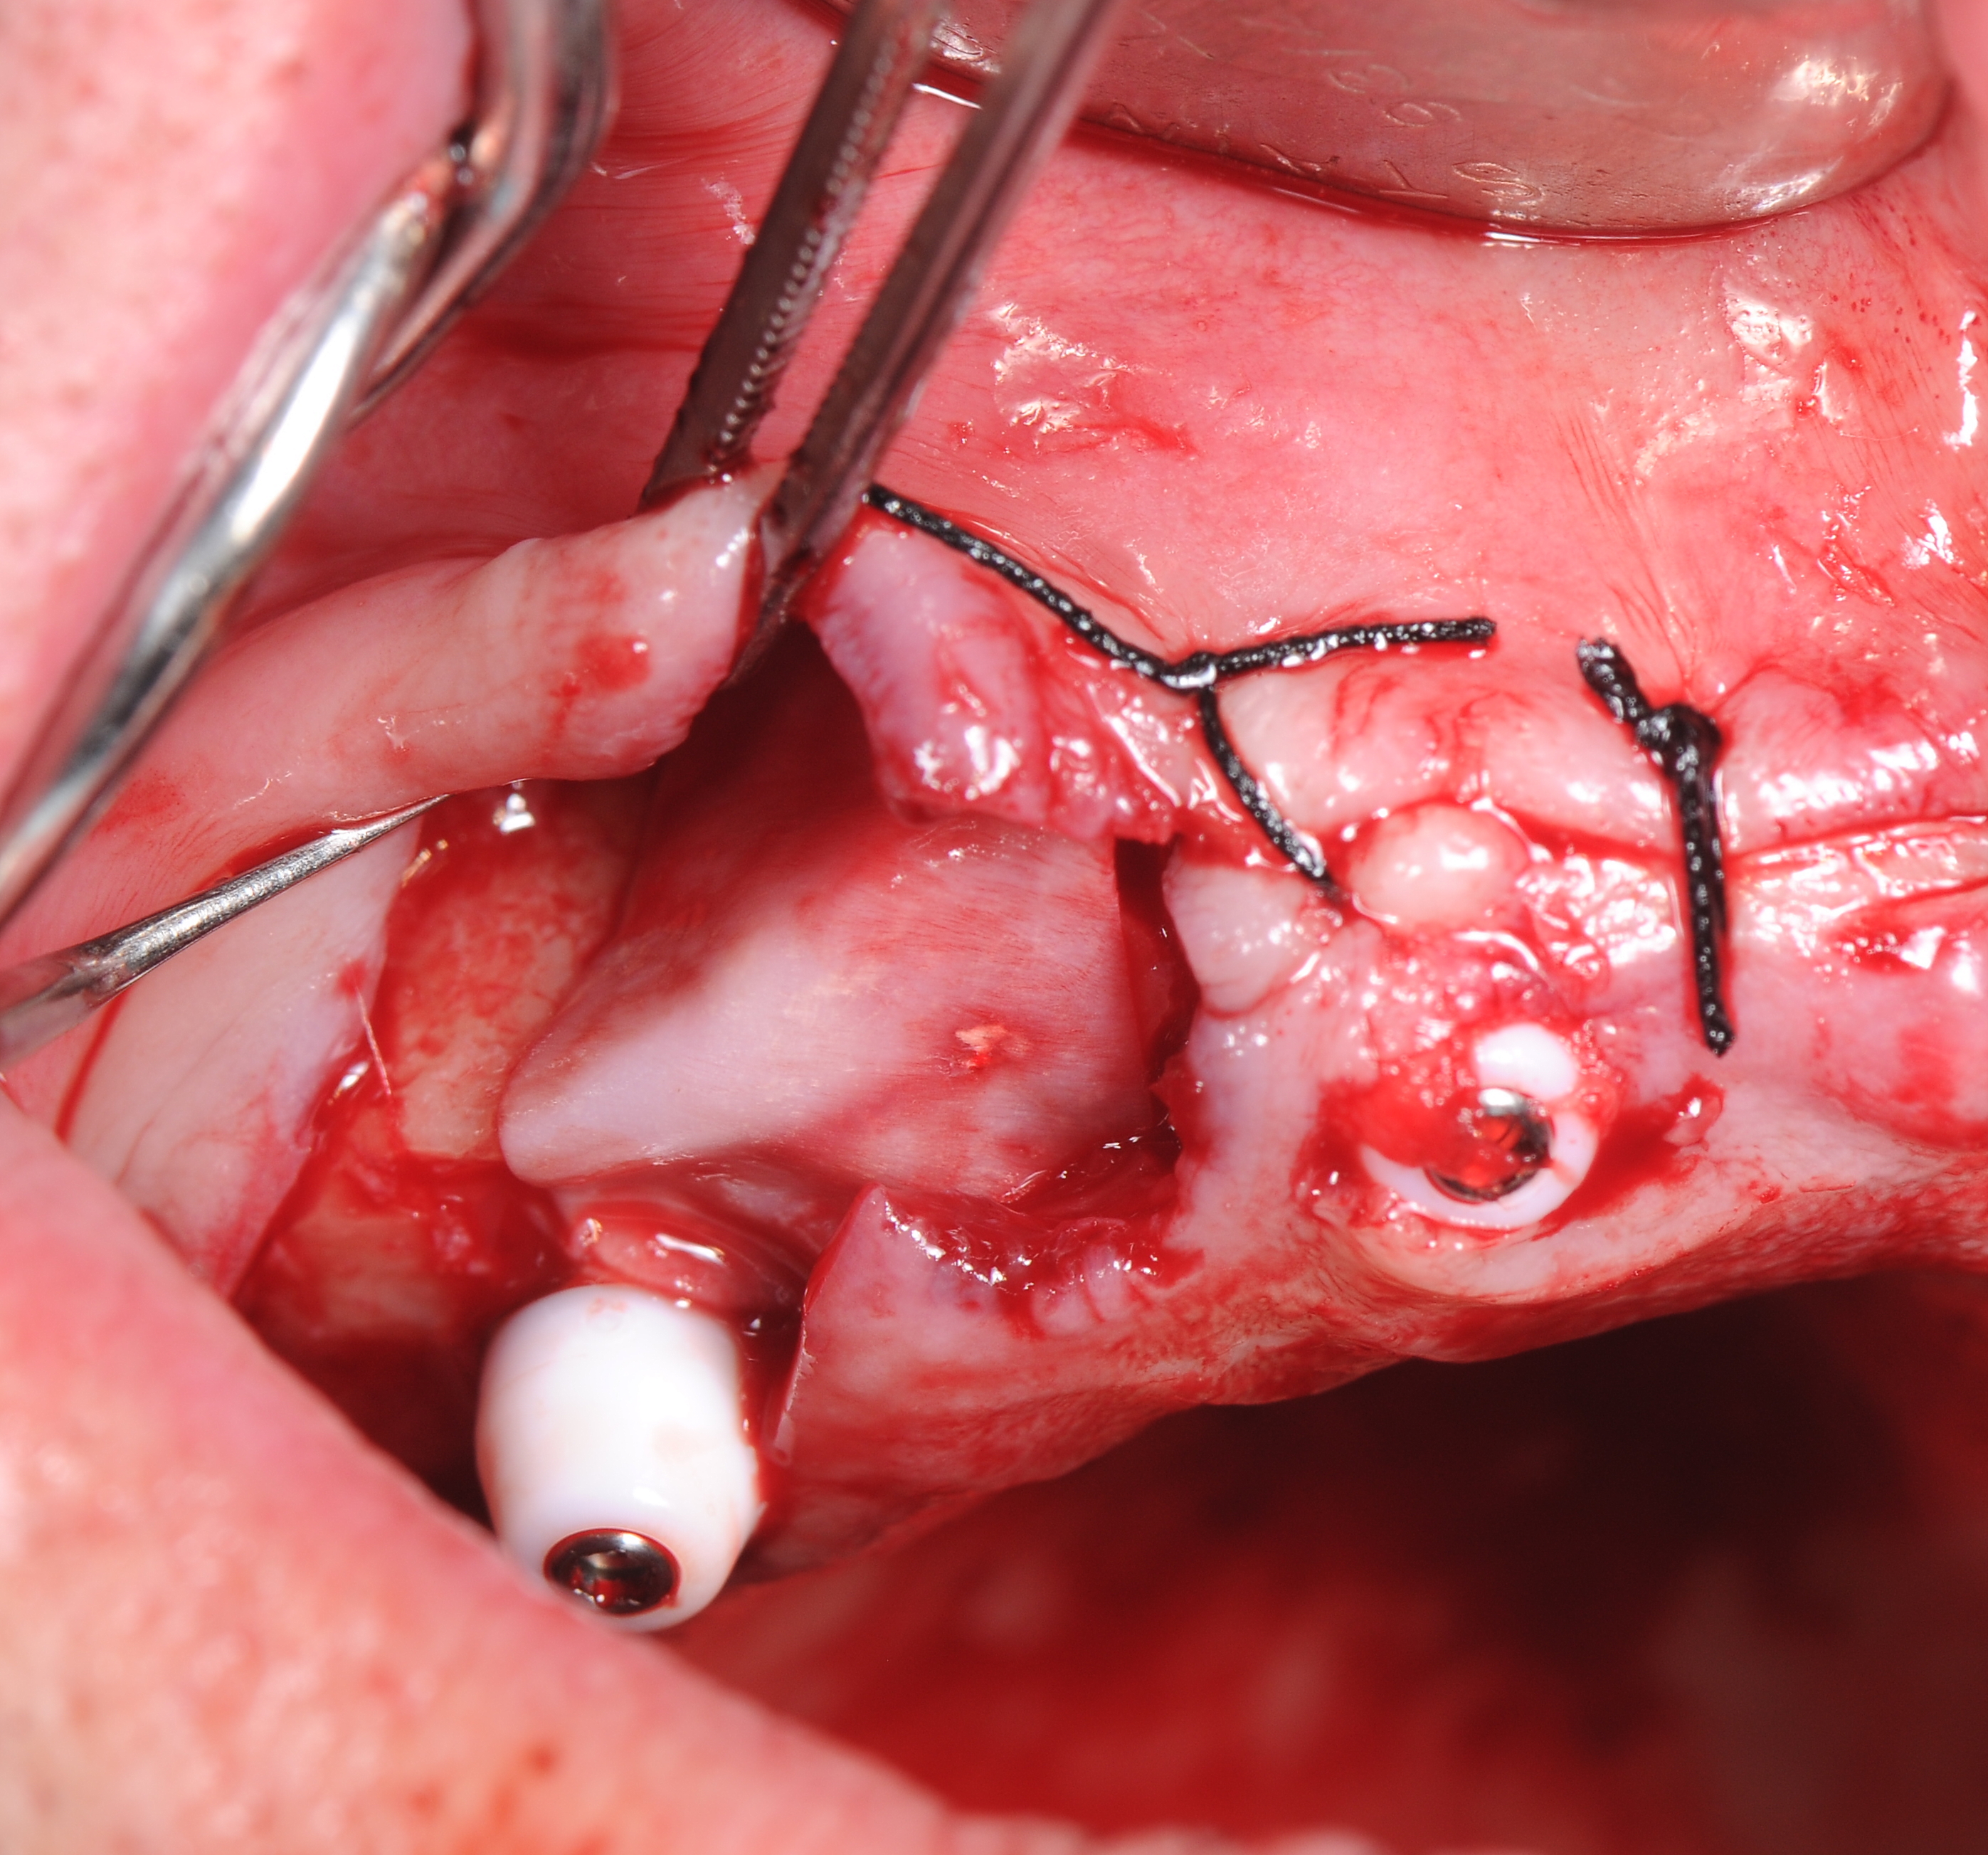

На «Multi – unit» абатменты зафиксированы пластиковые заживляющие колпачки. В небной части слизисто-надкостничного лоскута было сделано 2 перфорационных разреза в проекции фронтальных имплантатов, лоскут ротирован в вестибулярном направлении с расположением колпачков в зонах перфорации. Рана ушита шелковыми нитями без натяжения (рис 26,27,28).